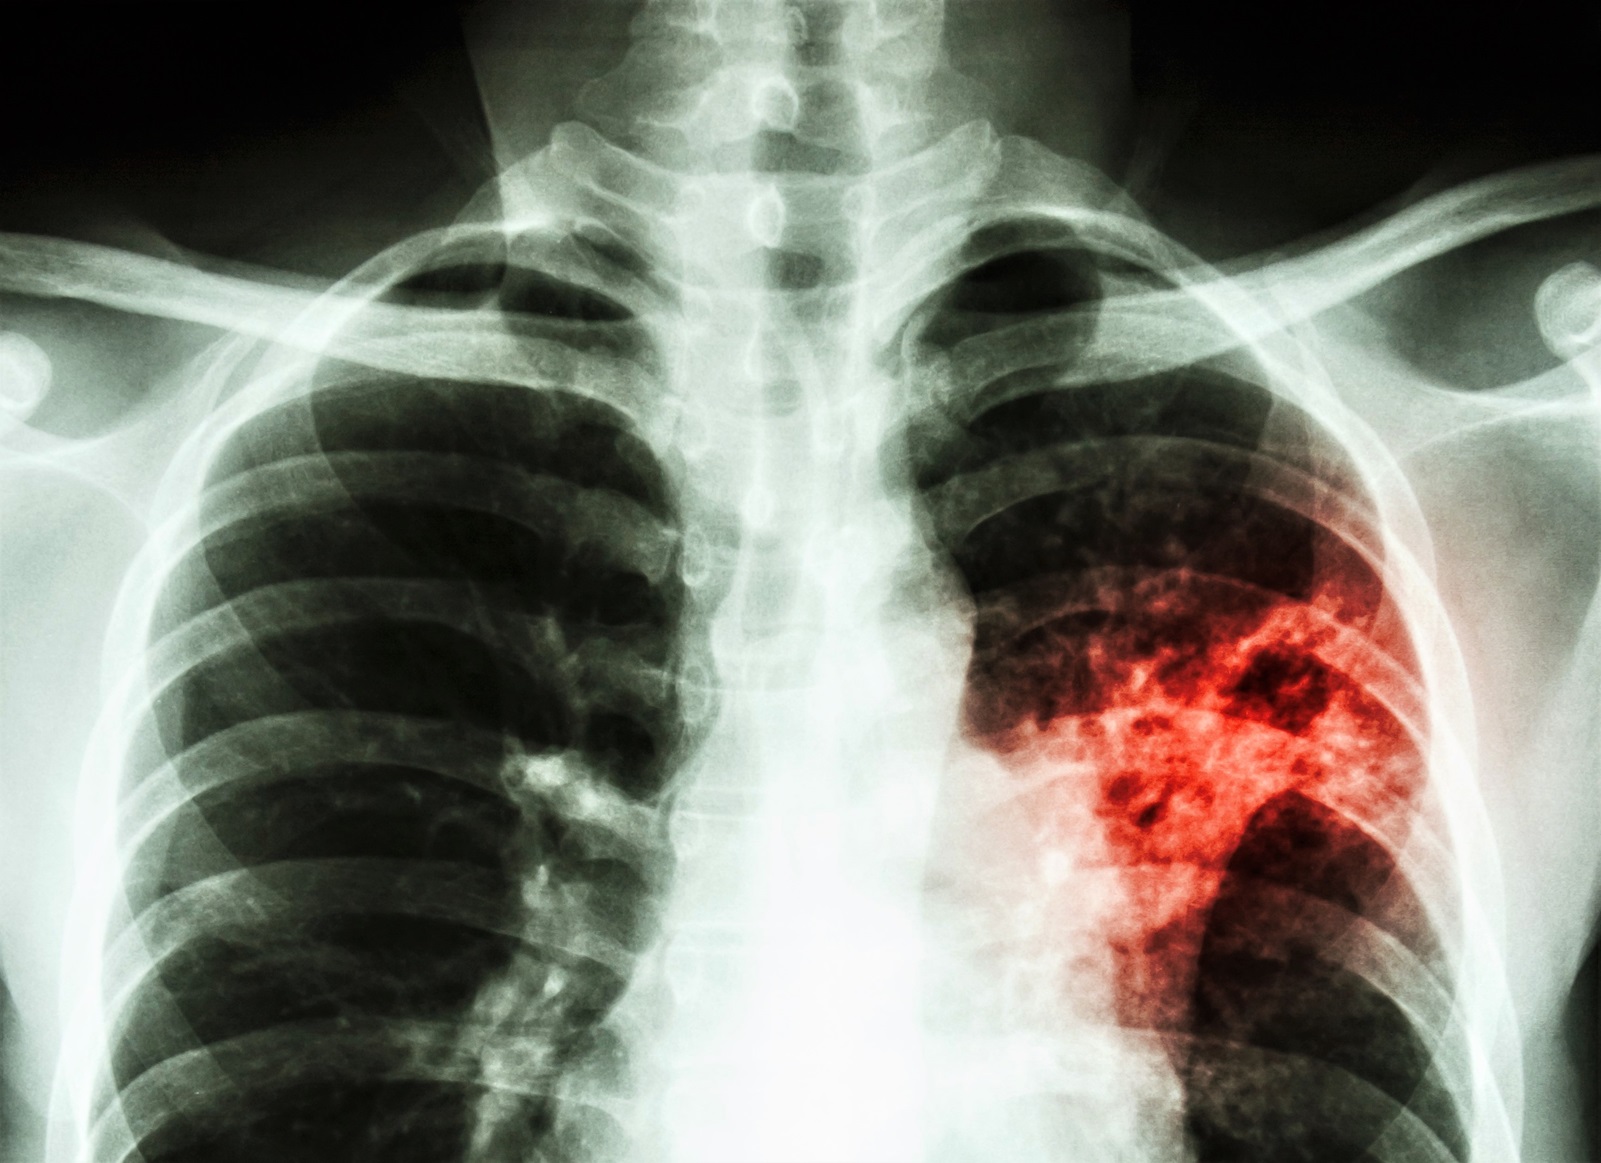

Måske kan visse smertestillende stoffer forværre infektion med tuberkulose

Noget peger på, at visse smertestillende stoffer, såsom ibuprofen, kan gøre luftvejsinfektioner med tuberkulose værre ved at påvirke immunsystemet. Det viser forsøg med mus udført på Statens Serum Institut (SSI). Om det også gælder for mennesker undersøges nu nærmere.

”Den ene gruppe mus fik TB, uden behandling, mens den anden blev behandlet med COXi-stofferne. I den sidste gruppe fandt vi op til 10 gange flere TB-bakterier i lungerne. En nærmere undersøgelse af musenes immunforsvar viste, at der var et fald i de såkaldte Th1 T-celler, som er særligt vigtige for at bekæmpe en TB-infektion”, siger Rasmus Skaarup Mortensen.